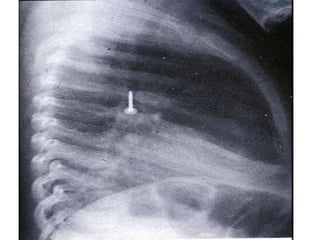

Note that the right primary bronchus is more vertical   while the left primary bronchus leaves at a more acute angle  (because of the heart).  This means that foreign objects are more likely to lodge in the  right  lung as it is more of a straight down route.

Note that theright primary bronchus is more vertical while the left primary bronchus leaves at a more acute angle (because of the heart). This means that foreign objects are more likely to lodge in the right lung as it is more of a straight down route.